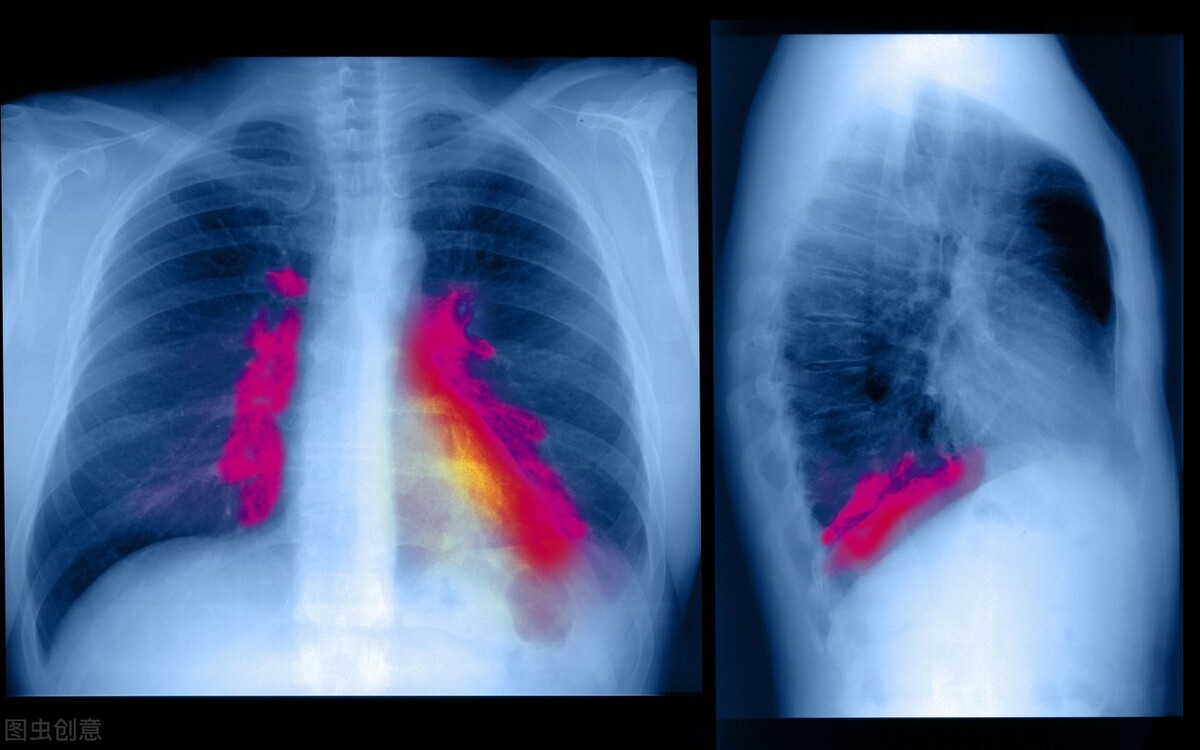

肺部感染是慢性支气管炎急性发作、急性支气管炎、肺炎、支气管扩张感染等肺部感染性疾病的总称,主要是指下呼吸道的感染 。肺部感染根据感染地点的不同,可以分为社区获得性肺炎和医院获得性肺炎,下面分别介绍二者的症状表现。